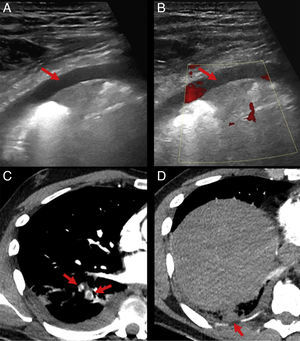

A male patient consulted due to cough, pleuritic pain and fever (38.3°C). Chest X-ray revealed consolidation in the right lower lobe (RLL) with effacement of the diaphragmatic silhouette. A diagnosis of complicated pneumonia was given, and a chest ultrasound was requested, which showed a small amount of pleural effusion and pleural-based, triangular subpleural consolidation (Fig. 1A), with no Doppler signal (Fig. 1B), possibly indicating pulmonary infarction. Chest CT-angiogram was performed, confirming filling defects in the posterobasal and laterobasal segmental arteries of the RLL (Fig. 1C) with subpleural peripheral opacity in the posterobasal segment of the RLL (Fig. 1D), with enhanced uptake corresponding to pulmonary infarction. The presence of “A-lines” in the ultrasound pattern has been described as indicative of pulmonary thromboembolism, with 81% sensitivity and 99% specificity if associated with deep vein thrombosis.1 Pulmonary infarction can be identified as a pleural-based wedge-shaped hypoechoic lesion with well-defined borders.2 In our patient, chest ultrasonography performed after an initial suspicion of complicated pneumonia was crucial for reaching the correct diagnosis.